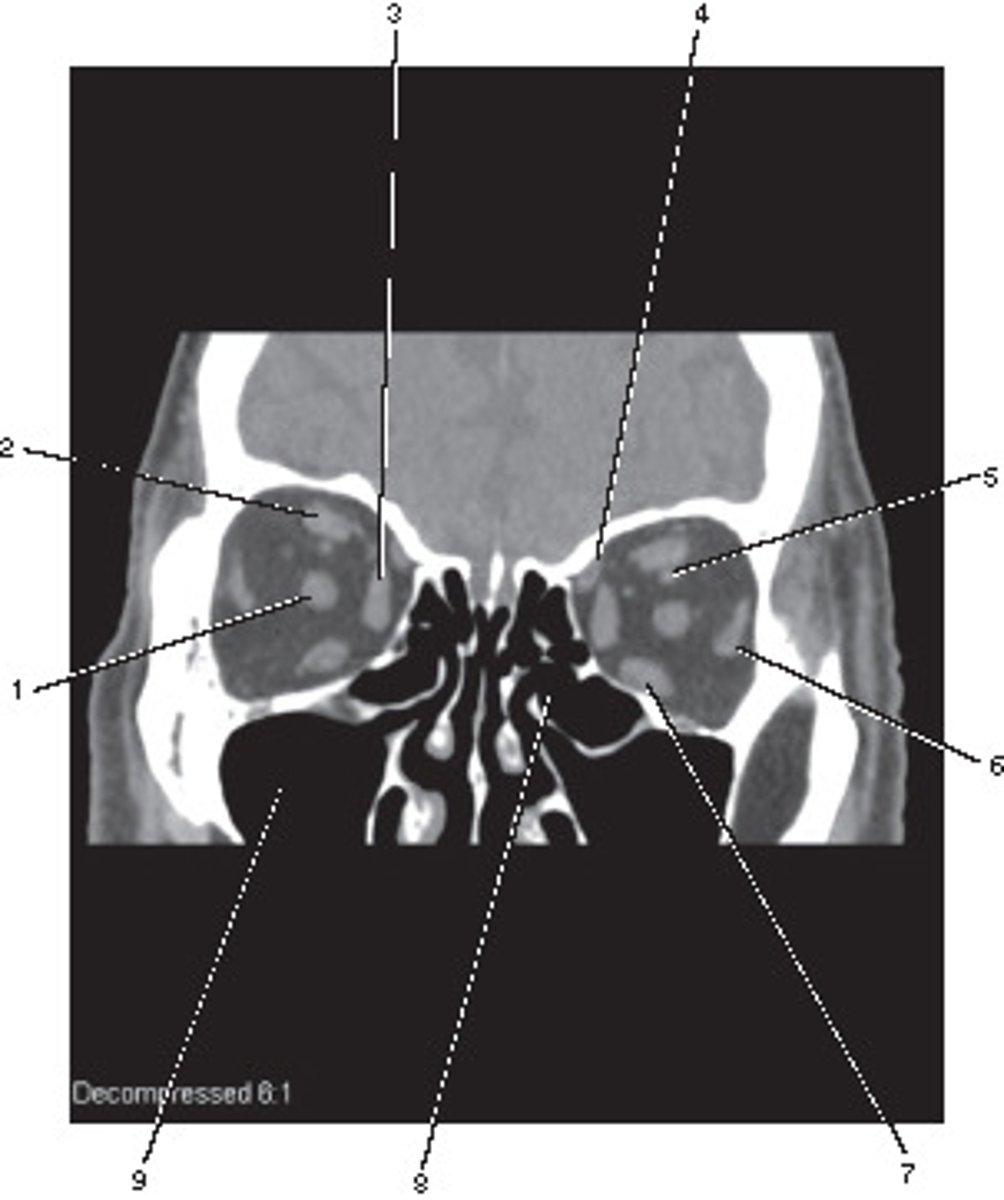

Number 2 corresponds to which of the following?

<p>Number 2 corresponds to which of the following?</p>

Number 5 corresponds to which of the following?

<p>Number 5 corresponds to which of the following?</p>

Inferior Vena Cava

Number 8 corresponds to which of the following?

Number 3 corresponds to which of the following?

<p>Number 3 corresponds to which of the following?</p>

Number 4 corresponds to which of the following?

<p>Number 4 corresponds to which of the following?</p>

Number 6 corresponds to which of the following?

<p>Number 6 corresponds to which of the following?</p>

16

New cards

Left Common Carotid Artery

17